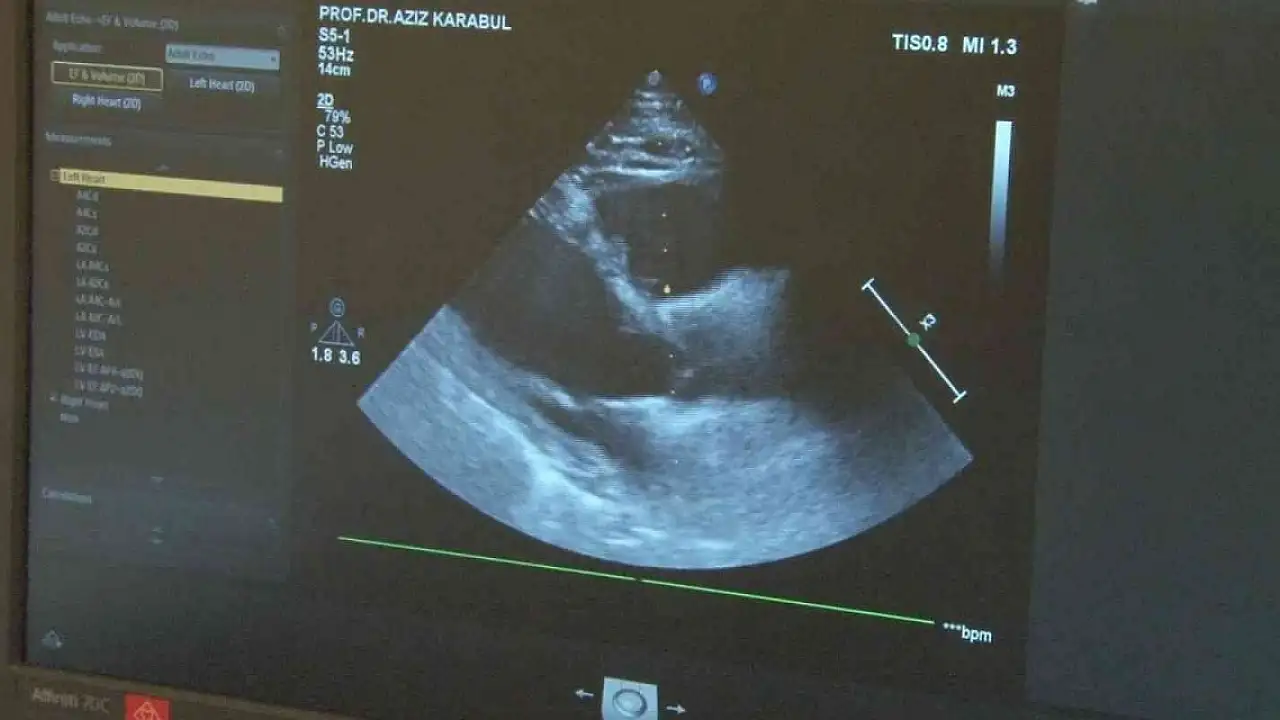

Son zamanlarda teknolojinin gelişmesi devam ederken birçok hastalıklıların tedavileri yaşam sürecini geçmişe göre uzattı. Bununla birlikte ileri yaş hastalığı olarak bilinen kalp yetmezliği ve damar tıkanıklığının önümüzdeki yüzyılda pandemi haline gelebileceğini, bu nedenle yaşam şekli modifikasyonlarının düzeltilmesi gerektiği açıklayan Memorial Dicle Hastanesi Kardiyoloji Uzmanı Prof. Dr. Aziz Karabulut, belirtileri tek tek sıralayarak önlem alınması için neler yapılacağını söyledi. Prof. Dr. Karabulut, "Gelecek projeksiyonunda önümüzdeki yüzyılda kalp yetmezliği pandemisi olabileceği ön görülmekte. Özellikle bir takım ritim bozuklukları, kalp yetmezliklerinin önümüzdeki 100 yıl içerisinde artacağı tahmin edilmekte. Bunun en önemli sebebi bütün dünyada beklenen ömür süresi uzuyor, kalp ve damar hastalıkları, kalp yetmezlikleri, ritim bozuklukları yaş ilerledikçe ortaya çıkıyor. Beklenen ömrün bir takım hastalıkları daha iyi tedavi edilebilir olması ortalama ömrü ve beklenen yaşı uzatıyor. Beklenen yaşam süresinin uzamasıyla beraber kalp yetmezliği belirtileri ve önümüzdeki yüzyılın kalp yetmezliği ve ritim bozuklukları açısından pandemi yüzyılı olabileceği tahmin edilmekte" dedi.